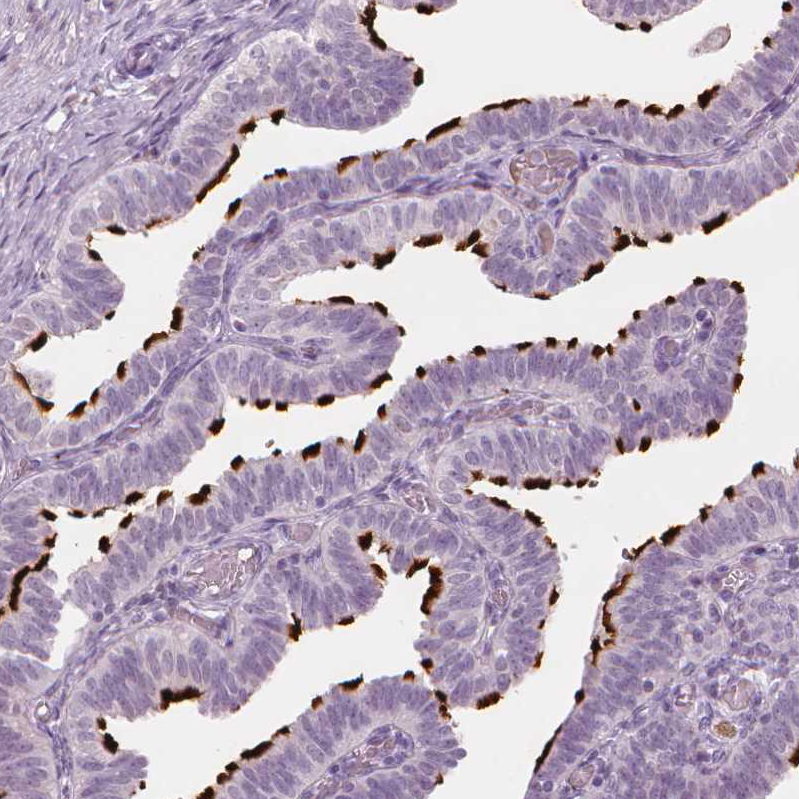

Immunohistochemical staining of human fallopian tube shows strong positivity in cilia.